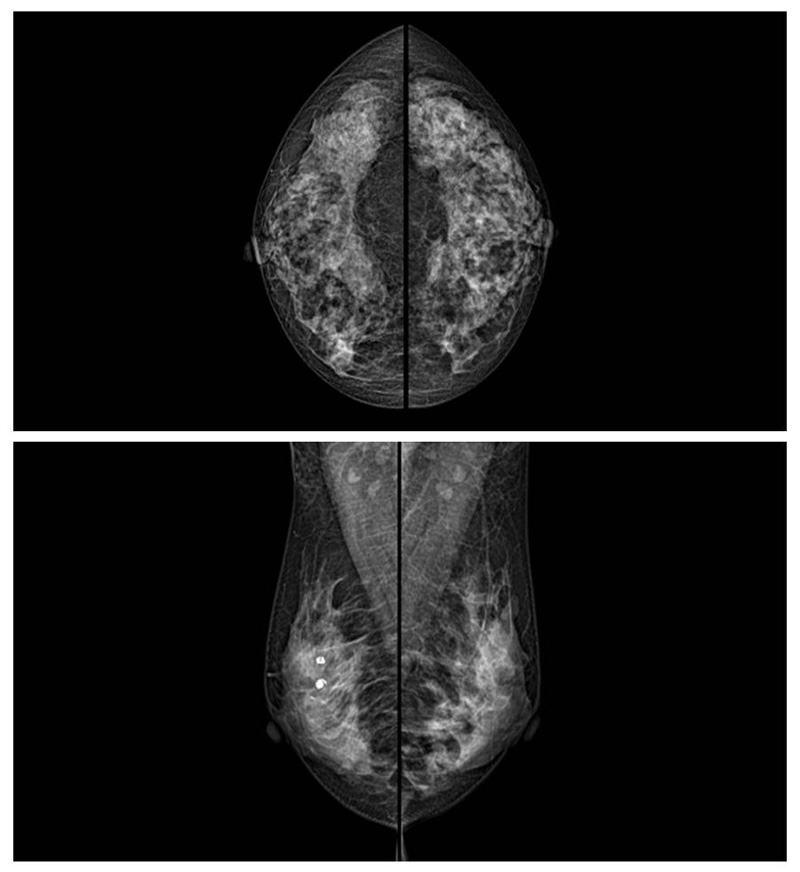

乳腺癌的發(fā)生率越來越高,已經是我們國家的癌癥之一已成為女性健康“頭號殺手”。乳腺DR可提高乳腺癌早期檢出率并精準定位。發(fā)現和診斷早期乳腺癌最有效的方法之一,明顯利大于弊女性都要重視乳腺的檢查。輻射很小最簡便、最可靠、無創(chuàng)性檢查手段,做一次乳腺DR的劑量相當于7周的正常生活。尤其是對于40歲以上的女性尤為重要,那么乳腺DR是怎么進行檢查的呢?我們來了解一下,為廣大朋友在檢查前有點心理準備。檢查時候是避開經期的前后,月經來后的7天左右比較合適。需要脫衣服檢查,根據拍片的擺位要求,有頭尾位置,內外斜位,還有側位。定點放大壓迫方法可以更細微清晰的檢查出病灶。